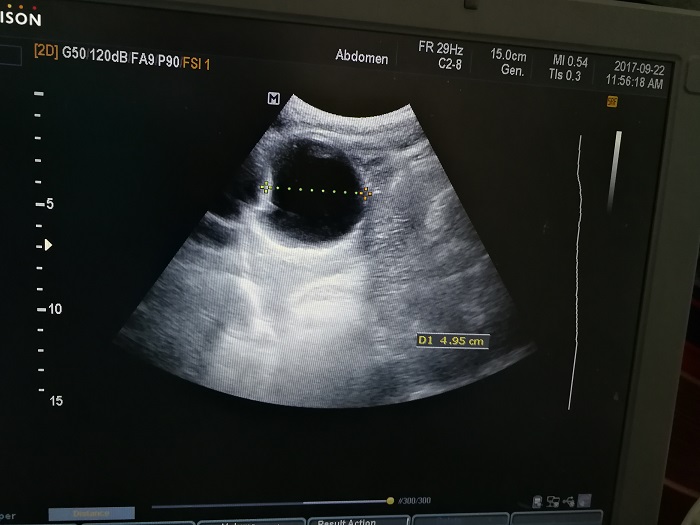

扎西(化名),男,15歲,包蟲病篩查陽性,牧區(qū)孩子,家里有牦牛20頭、羊200只,狗1條,牛羊自家屠宰,飲用河水。

●革吉縣初級中學篩查點 · B超現(xiàn)場圖片

除了包蟲病篩查外,連續(xù)三天的學校體檢我醫(yī)療隊發(fā)現(xiàn)腎積水、腎囊腫、腎結(jié)石的學生患者較多,我們將體檢到的相關(guān)臟器疾病同時間反饋給了班主任,讓他們密切觀察病情,及時通知家長。劉冬梅醫(yī)生建議,學校要組織學生多飲水,同時多加觀察本地水質(zhì)情況。

本次篩查,革吉縣初級中學共篩查學生498例,陽性3例,疑似2例。